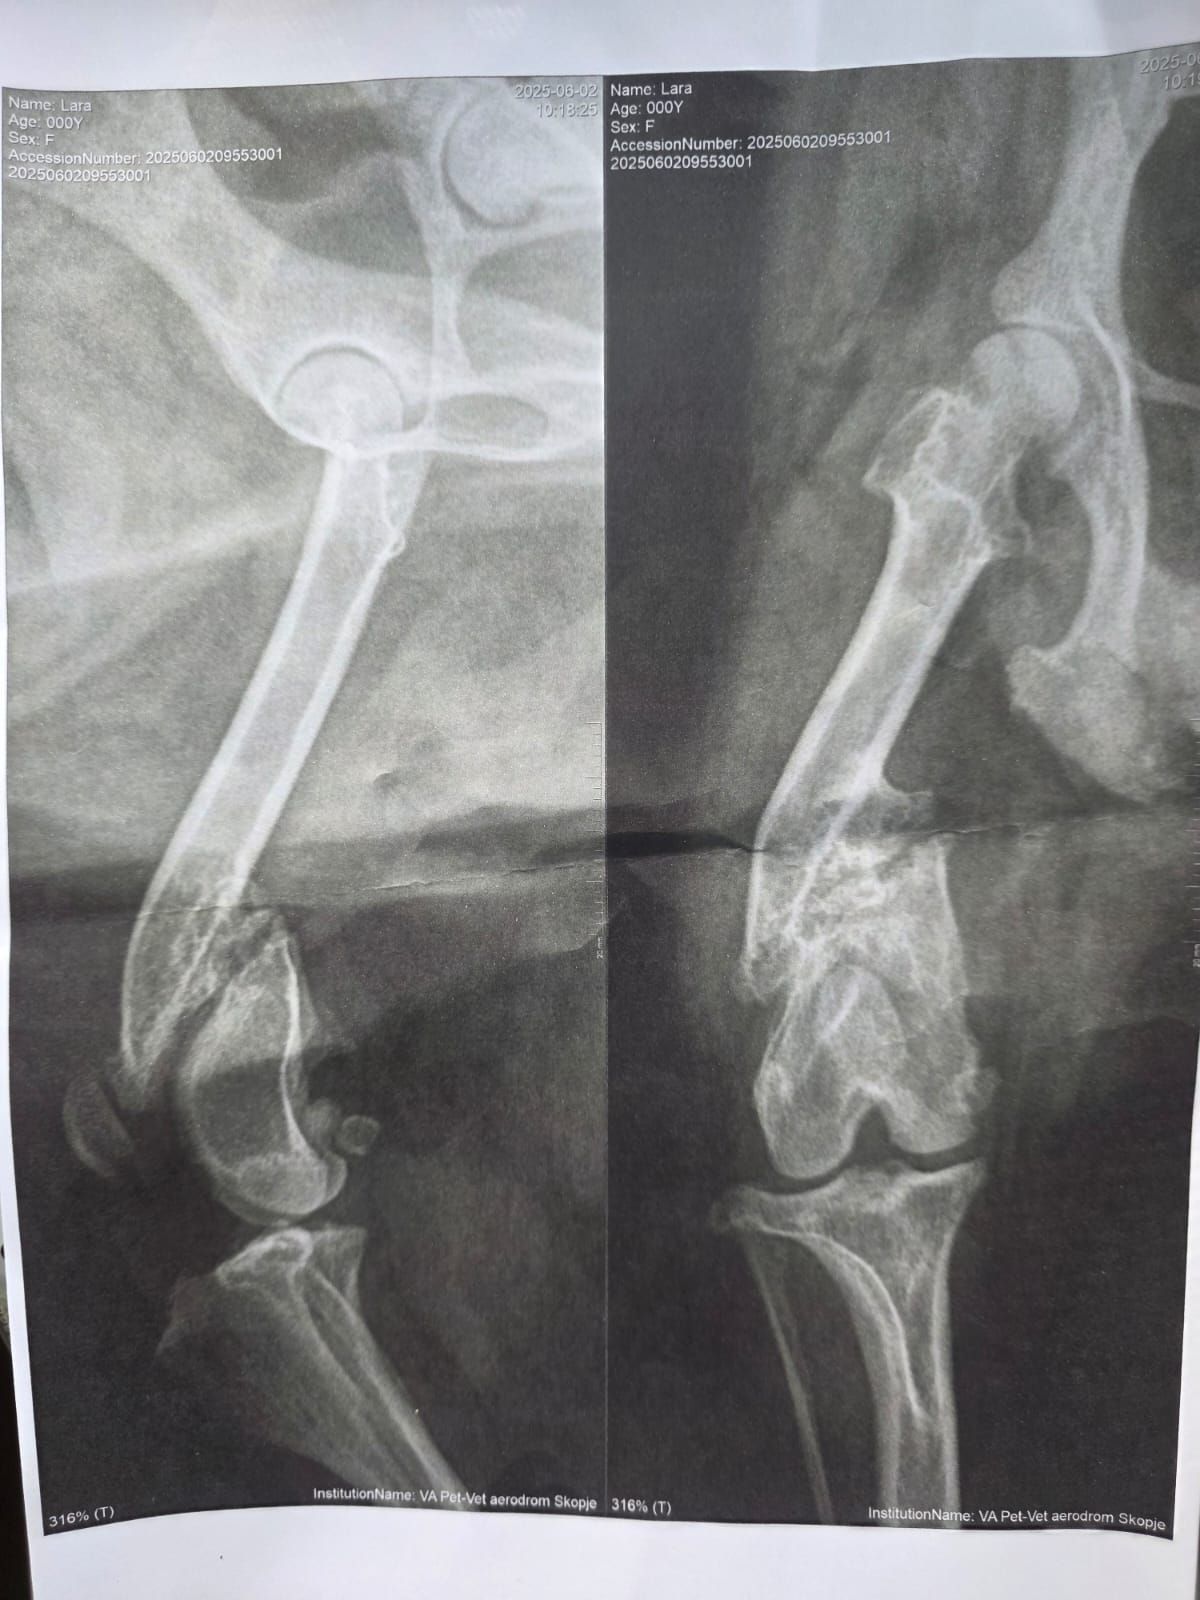

Zusätzlich hat sie ein gebrochenes Vorderbeinchen, was einfach nicht heilen will, das heißt es ist dauer-gebrochen. Dass das kein Zustand auf Dauer ist, ist jedem klar, doch die Tierärzte in Nordmazedonien sind sich uneinig, was zu tun ist. Lara bekommt deshalb jeden Tag Schmerzmittel, die aber nicht ausreichen.

Es geht auch um eine wahrscheinlich anstehende Beinamputation, doch vielleicht kann ein guter Chirurg das Blatt doch noch wenden.